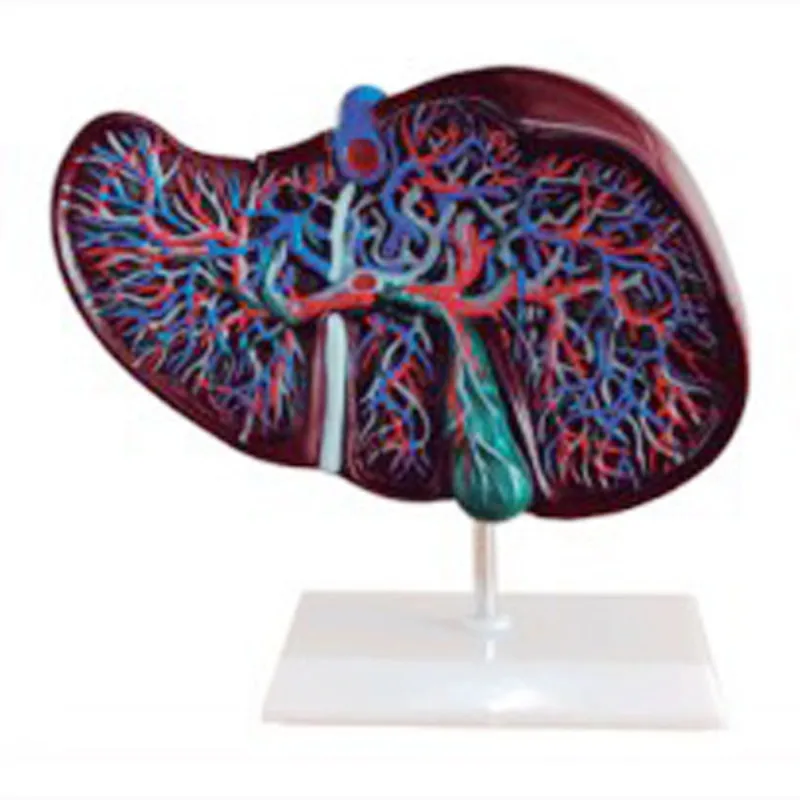

Цветная анатомическая модель печени, симулятор медицинской медицины для студентов, научные источники для обучения, технические характеристики

aliexpress.ru